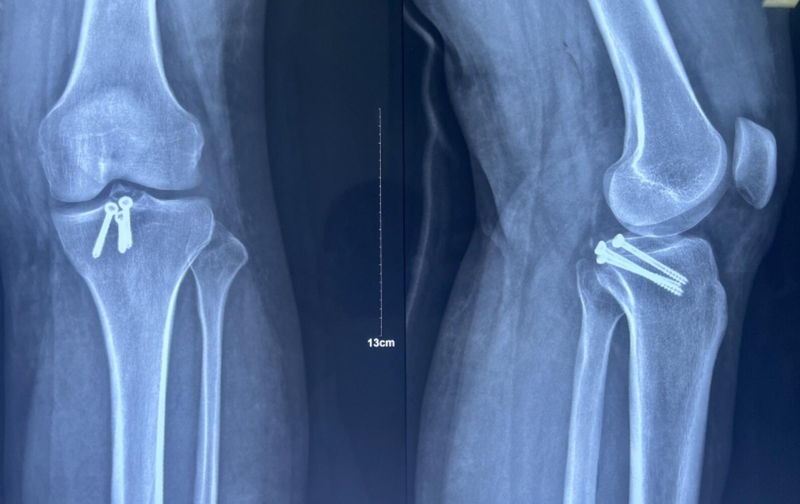

x男,30岁,体重100kg,在五楼擦玻璃时坠落到四楼致伤2天。

诊断:左胫骨平台后柱骨折,后交叉韧带撕脱骨折,左踝关节pilon骨折3型。

术前影像学资料:

图7 前交叉韧带撕脱骨折与平台后柱骨折